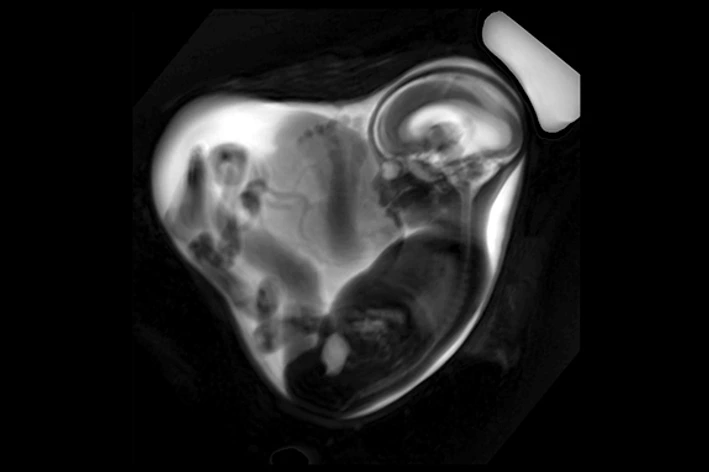

LMU Klinikum Fetale MRT Overview

Pregnancy and COVID-19: Reduced Lung Volume in the Unborn

By the use of fetal magnetic resonance imaging (MRI), scientists and physicians from Helmholtz Munich and LMU University Hospital Munich have discovered a reduction in lung volume in fetuses from mothers with an uncomplicated SARS-CoV-2 infection…